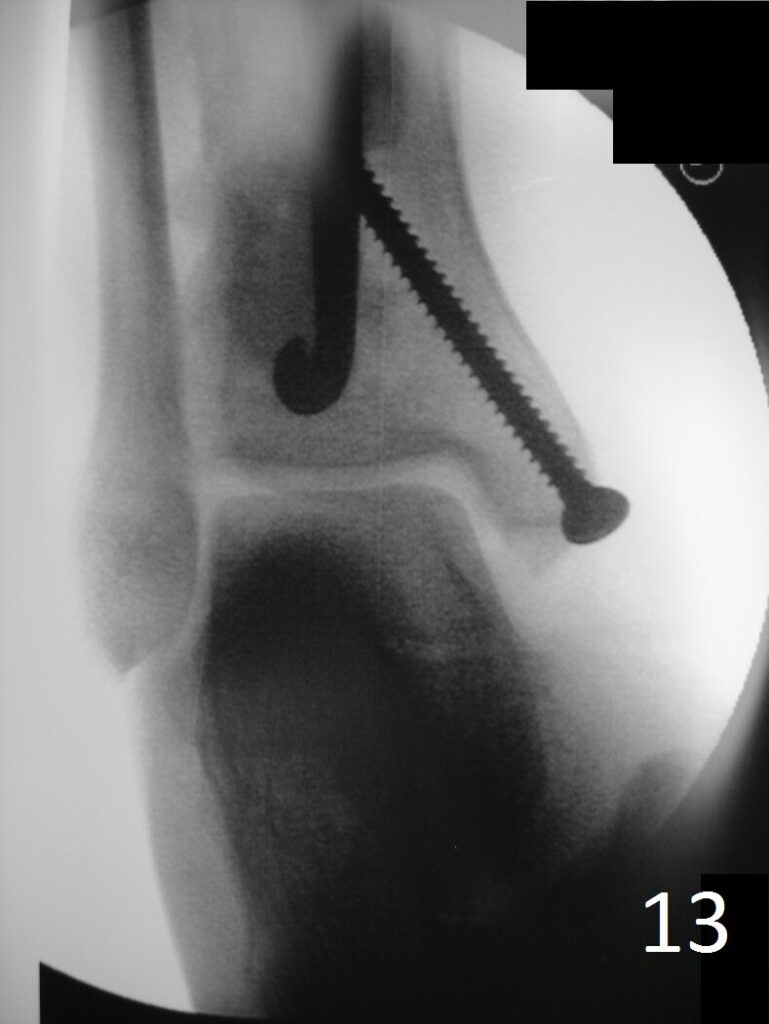

Fig. 13: Postoperative image of distal tibia-fibula shows the fixation.